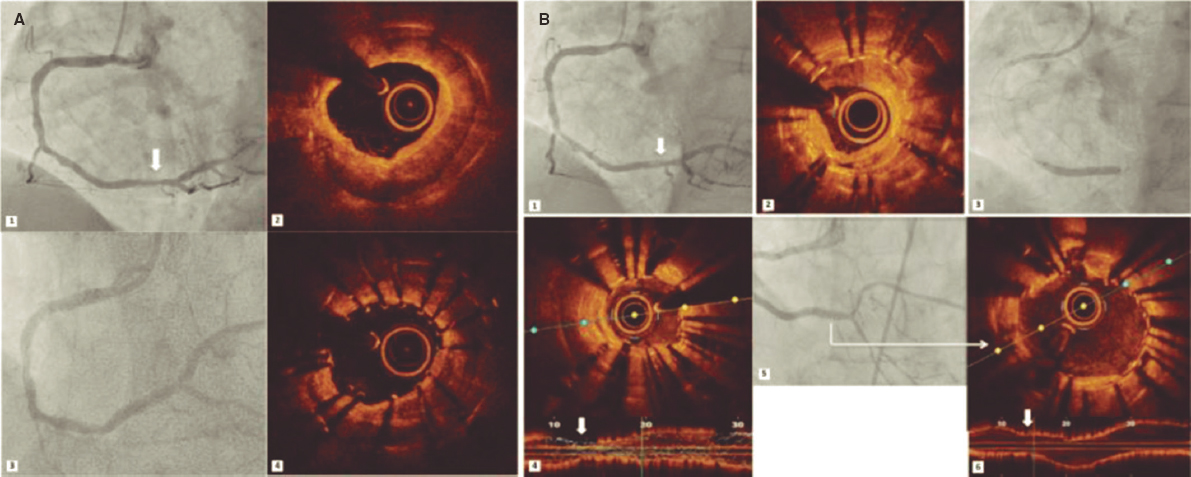

8. Back in the RV, the perpendicularity of the clip with respect to the target coaptation line should be confirmed on the transgastric short axis view. Then, the grasping view should be looked for, that is, the view that better shows the target leaflets and the clip with wide open arms. It is essential to have good ultrasound imaging during grasping to guarantee the correct insertion of the leaflets and the perpendicularity of the arms of the clip. Repeated suboptimal captures of the leaflets should be avoided to not cause excessive damage (TV leaflets are thinner and more fragile compared to the mitral valve leaflets) (figure 7).

Figure 7. Examples of grasping view. A and D: patient 1, grasping from the intercommissural view at 75° and from the direct grasping view at 125°. B and E: patient 2, direct grasping view acquired at 0° and 160°. C and F: right, anterior, oblique projection to steer the movement of the clip. A, anterior; S, septal.

9. Once the leaflets have been captured, their insertion should be confirmed through multiple 2D TEE views. Also, the presence of tissue bridges should be verified (though 3D TEE views). Multiplane is very useful for assessment purposes. A TTE or an intracardiac echocardiography should be used in cases of uncertain leaflet insertion. The TV mean gradient should be measured to discard stenosis; in general, mean gradients > 3 mmHg are not recommended (figure 8).

Figure 8. A-D: grasping assessment in multiple views for leaflet insertion assessment and reduction of tricuspid regurgitation.